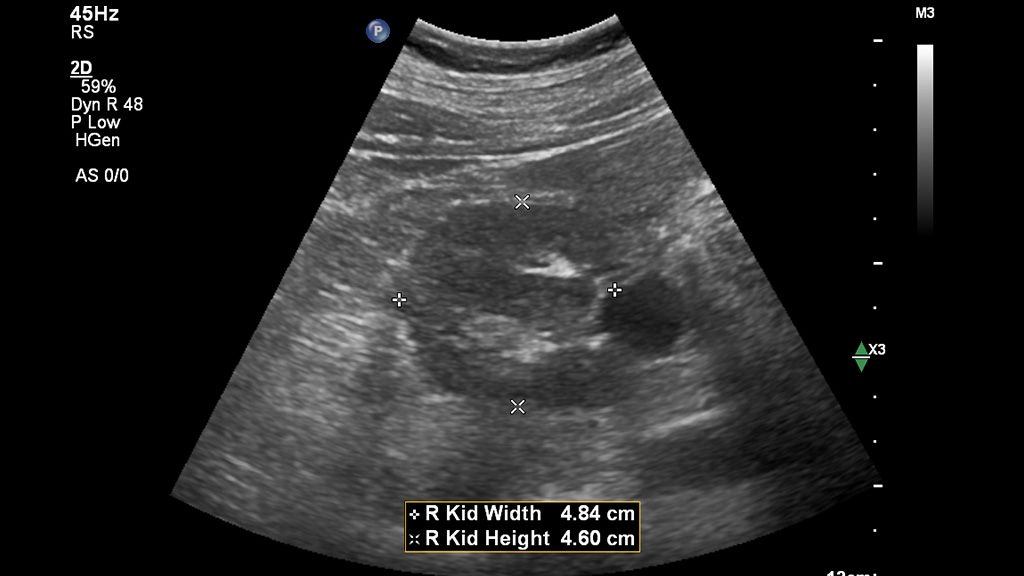

Standard workflow vs. Auto Measure Abdomen workflow

See how much time you can save with Auto Measure Abdomen in this side-by-side workflow comparison video.

The widespread use of this technology in a general population could be helpful in screening for advanced chronic liver disease, especially considering that a complete study can be done in under three minutes using a non-invasive method for chronic liver disease.